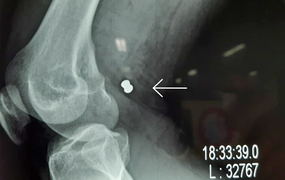

Khi đang làm vườn, người phụ nữ bất ngờ bị dị vật găm vào đầu phải đi cấp cứu, bác sĩ phát hiện dị vật là một đầu đạn kim loại nằm dưới da vùng chẩm.